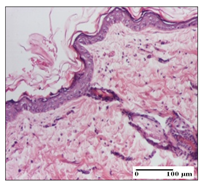

![]() | ![]() | ![]() |

| severe dermal collagenization (S1, D1, G0) | congestion in hypodermis (S0, D0, G0) | severe dermal collagenization (S0, D0, G0) |